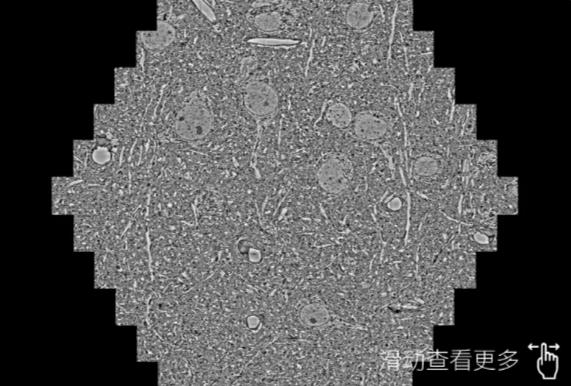

鼠腦切片。左圖使用蔡司掃描電鏡MultiSEM706對165μmx143pm麵積區域成像,耗時僅需1.5秒。右圖為鼠腦切片中30μm區域放大效果。樣品由芝加哥大學B.Kasthuri提供。